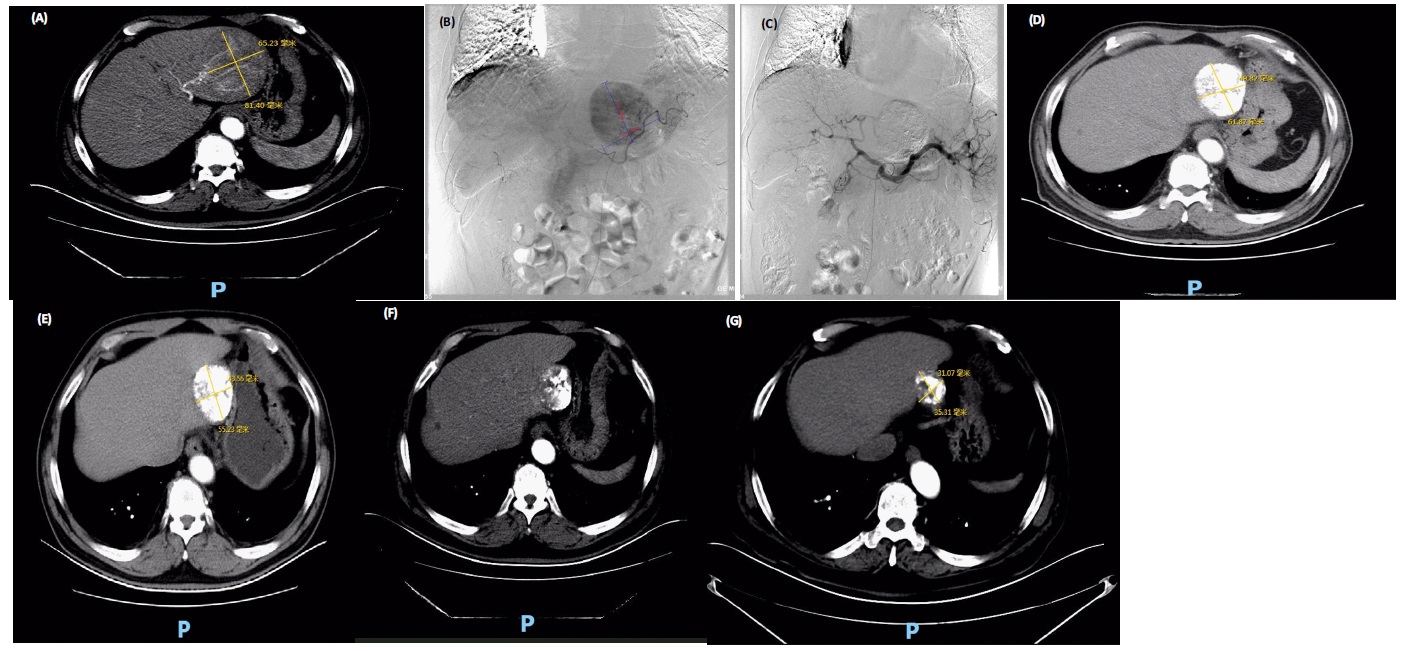

Figure 3: Patient Xu XX, September 25, 2017, physical examination of the upper abdomen enhanced CT examination suggested that the left lobe of the liver 81.40mm * 65.23mm occupancy, arterial phase enhancement was obvious, portal phase enhancement faded, overall consistent with HCC “fast in and fast out” performance; Figure 3b: Intraoperative DSA imaging can be seen in the tumor significantly; Figure 3c shows the intraoperative DSA image on November 15, 2017; Figure 3d shows the enhanced CT of upper abdomen on January 16, 2018; Figure 4e shows the enhanced CT of upper abdomen on May 15, 2018; Figure 3f shows the enhanced CT of upper abdomen on January 4, 2019; Figure 3g shows the enhanced CT of upper abdomen on April 23, 2021. The enhanced CT of the upper abdomen on April 23, 2018 shows a progressively decreasing lesion with good iodized oil deposition.